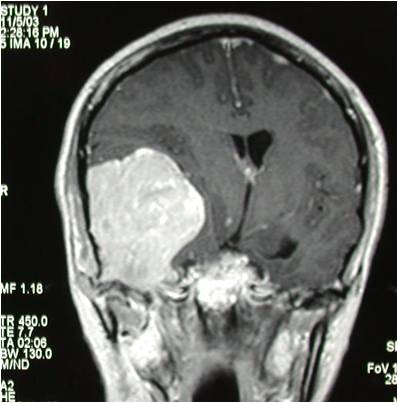

巨大中颅底脑膜瘤切除术

术后mRI见肿瘤切除满意